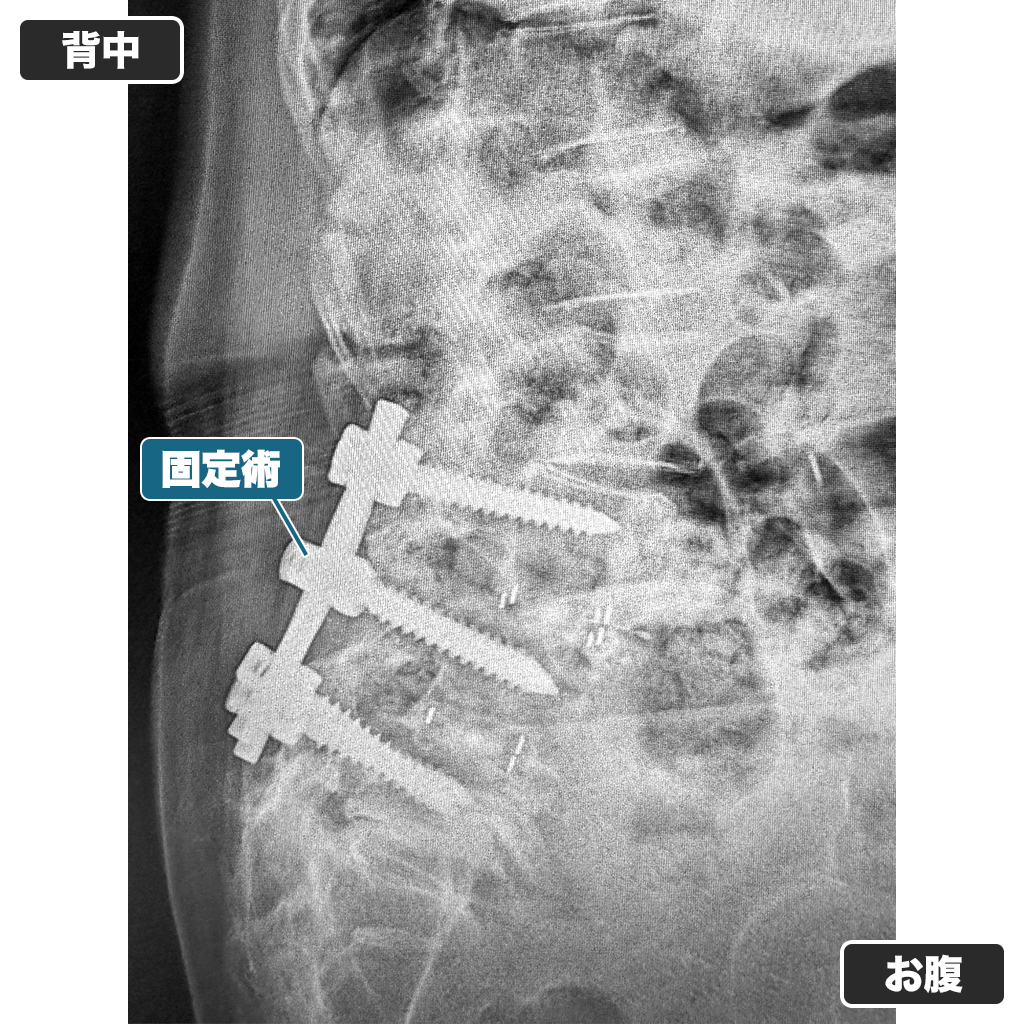

レントゲン検査

腰のレントゲン写真ですが、脊椎固定術(ボルトでの固定)がされています。